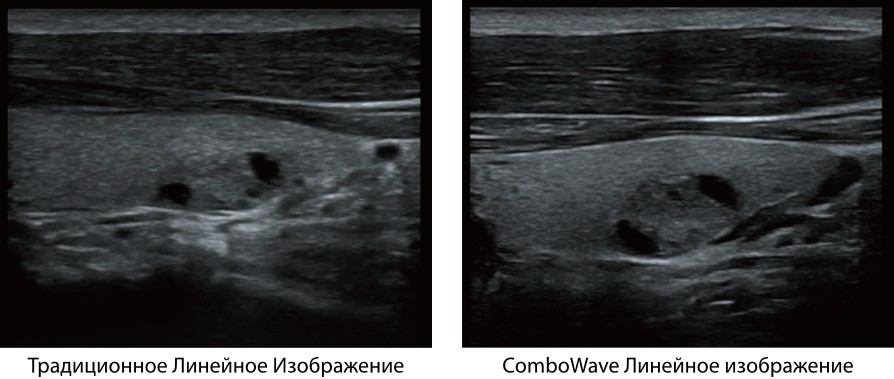

ComboWave

ComboWave - ―ç―²–Ψ ―É–Ϋ–Η–Κ–Α–Μ―¨–Ϋ–Α―è ―²–Β―Ö–Ϋ–Ψ–Μ–Ψ–≥–Η―è –¥–Μ―è –Μ–Η–Ϋ–Β–Ι–Ϋ―΄―Ö –¥–Α―²―΅–Η–Κ–Ψ–≤. –ë–Μ–Α–≥–Ψ–¥–Α―Ä―è –Ω―Ä–Η–Φ–Β–Ϋ–Β–Ϋ–Η―é –Ϋ–Ψ–≤–Ψ–≥–Ψ ―²–Η–Ω–Α –Κ–Ψ–Φ–Ω–Ψ–Ζ–Η―²–Ϋ–Ψ–≥–Ψ –Ω―¨–Β–Ζ–Ψ―ç–Μ–Β–Κ―²―Ä–Η―΅–Β―¹–Κ–Ψ–≥–Ψ –Φ–Α―²–Β―Ä–Η–Α–Μ–Α –¥–Α―²―΅–Η–Κ–Η DC-40 ―¹ Full HD –Η–Φ–Β―é―² –±–Ψ–Μ–Β–Β –≤―΄―¹–Ψ–Κ―É―é –Ω―Ä–Ψ–Η–Ζ–≤–Ψ–¥–Η―²–Β–Μ―¨–Ϋ–Ψ―¹―²―¨ –±–Μ–Α–≥–Ψ–¥–Α―Ä―è ―Ä–Α―¹―à–Η―Ä–Β–Ϋ–Ϋ–Ψ–Φ―É –Α–Κ―É―¹―²–Η―΅–Β―¹–Κ–Ψ–Φ―É ―¹–Ω–Β–Κ―²―Ä―É –Η –±–Ψ–Μ–Β–Β –Ϋ–Η–Ζ–Κ–Ψ–Φ―É –Α–Κ―É―¹―²–Η―΅–Β―¹–Κ–Ψ–Φ―É –Η–Φ–Ω–Β–¥–Α–Ϋ―¹―É.